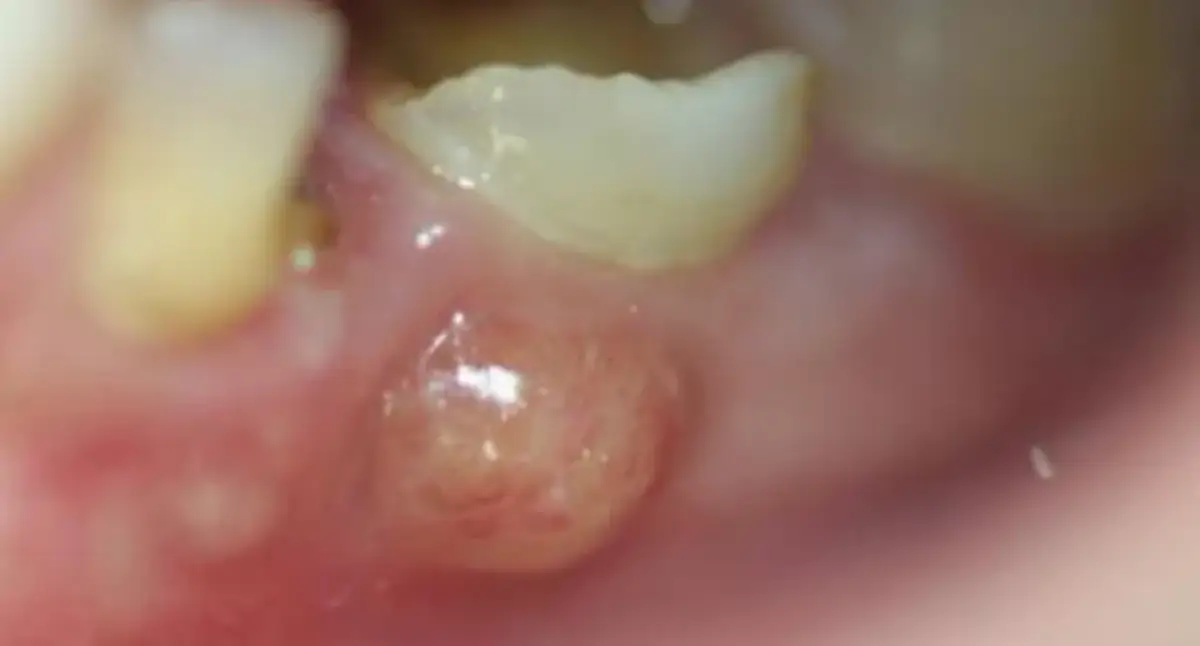

Zanim przejdziemy do leczenia, warto zrozumieć, czym właściwie jest ropień na dziąśle. W uproszczeniu, ropień to ograniczony zbiornik ropy, który powstaje w wyniku infekcji bakteryjnej. Może być to ropień przyzębny (zlokalizowany w tkankach otaczających ząb) lub ropień okołowierzchołkowy (powstający na końcu korzenia zęba, w kości). Ta bolesna gulka, którą często widzisz lub wyczuwasz na dziąśle, jest niczym innym jak sygnałem alarmowym Twojego organizmu, że toczy się w nim poważna walka z bakteriami.

- Widoczne, zaczerwienione i tkliwe uwypuklenie na dziąśle: W miejscu ropnia pojawia się opuchlizna, często przypominająca gulę, która jest czerwona, błyszcząca i bardzo wrażliwa na dotyk.